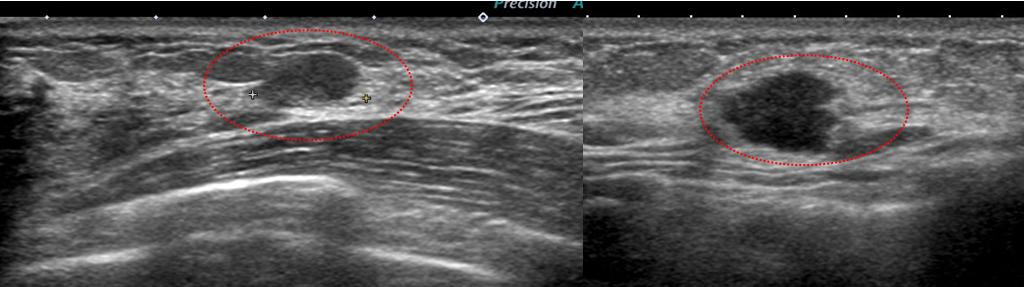

Aクリニック 初診時US ①

Aクリニック 初診時US ②

Aクリニック 初診時US ③

これを自信たっぷり「大丈夫だ、線維腺腫」っていったわけ?

とても画像だけで「線維腺腫と言い切れるレベル=きれいな楕円形」ではないよね??

左と右(「なのは」さんのAクリニックでの初診時)比べてください。

実は左も癌です。

右の方がよっぽと「癌らしく」見えませんか?

Aクリニック 初診時US ④